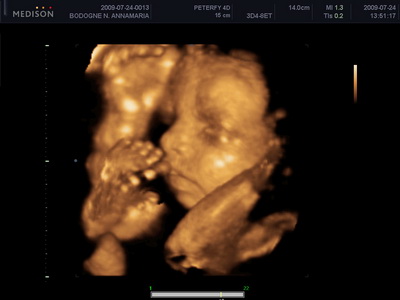

Mi megvagyunk, növögetünk ezerrel. Pénteken voltunk 4d-n, minden rendben van. Lilike most már biztos hogy Lilike, nem szégyenlős a drágám, rendesen bepucsított és szép kis hurija is van. 1000g-nak mérték és azt mondta a doktornő, hogy készüljünk, hogy szép nagy baba lesz. Nem a súlya lesz óriási, hanem szép hosszú lesz, lehet hogy 58-60 cm :lol: Mondjuk erre számítottunk mert mi se vagyunk alacsonyak :lol: Egyébként tiszta apja a kis drága. Nagy csókos szája van és kis kerek arcocskája. Teljesen beleszerettem :lol: Még puszit is küldött nekünk a kis husi szájával. Teszek fel pár képet nektek.

Kép

Kis csókos szájú

Vitathatatlan nunis

Nyitott szemmel